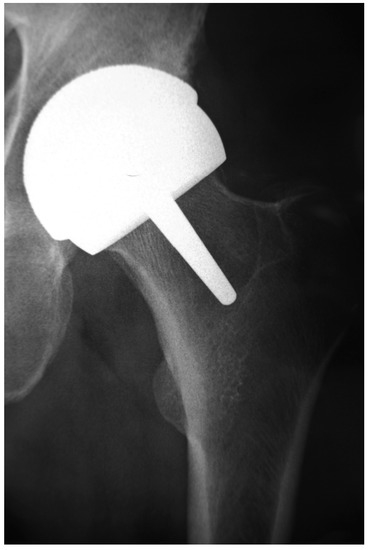

Metal-on-Metal (MoM) bearings for hip arthroplasty consisting of cobalt-chromium-molybdenum (CoCrMo) alloys were first introduced in the sixties by McKee and Farrar [1] and by Ring [2]. As early as 1968, Papps et al. published their findings on the toxicity of CoCrMo particles on tissue cultures [3], endorsed by the research of Trevor Rae, who, in 1979, concluded: ‘after the implantation of orthopaedic prostheses, metals can dissolve from the alloys used, some of the metals are toxic. […] From the biological standpoint, in view of the very much higher levels of soluble metal produced, metal against metal bearings should be avoided.’ [4] By that time, however, MoM hip arthroplasties had been abandoned for the low friction metal-on-polyethylene (MoP) hip replacements developed by Sir John Charnley [5]. When an increasing number of these MoP total hip arthroplasties (THA) had to be revised because of progressive loosening and extensive osteolysis caused by a macrophage response to polyethylene (PE) wear particles [6] whilst hip simulator studies were demonstrating substantially less volumetric wear from MoM bearing surfaces [7,8], MoM hip articulations were reintroduced to solve the problem of polyethylene (PE) particle-induced osteolysis. The imperfections regarding geometry, tolerance and metallurgy (low-carbon content associated with higher wear) of the first generation MoM articulations were resolved in the second generation high carbon content Metasul® MoM bearings (Sulzer/Centerpulse, Winterthur, Switzerland, 1988), which exhibited very promising short- and medium term results [9]. Furthermore, in the nineties, modern MoM hip resurfacing arthroplasty (HRA) (Figure 1) was proposed to address the inferior clinical results of THA in young and active patients, including the high dislocation rates of the 22 and 28 mm diameter femoral heads of the low friction MoP THA [10].

Figure 1.

Radiograph of a Metal-on-Metal (MoM) Hip Resurfacing Arthroplasty (HRA).